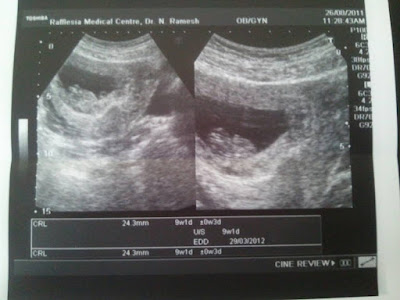

Friday, August 26, 2011

Baby Bae 9 Weeks 1 Day

Taken on 26th Aug 2011, 24.3mm

Published with Blogger-droid v1.7.4